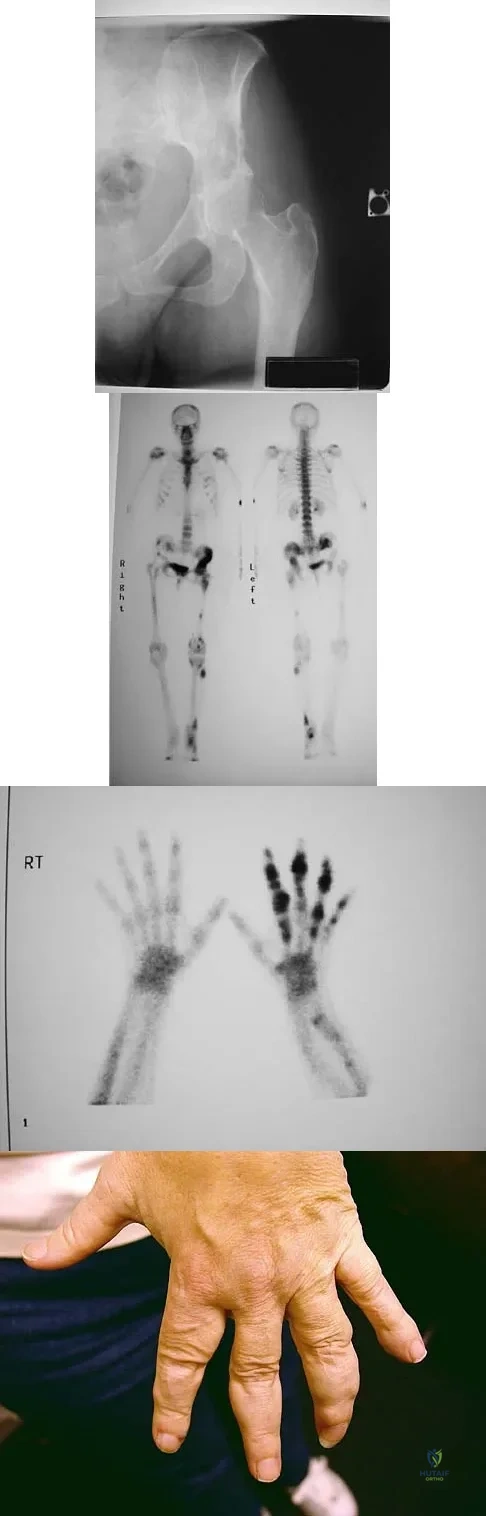

Question 94High Yield

Figure 15a shows the radiograph of a patient who has a chondrosarcoma of the acetabulum. Bone scans are shown in Figures 15b and 15c. Numerous soft subcutaneous masses are present. A clinical photograph of the hand is shown in Figure 15d. What is the most likely diagnosis?

Explanation